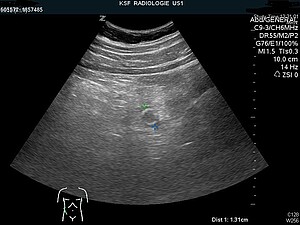

Meist ist die Diagnose der Appendizitis eine klinische Diagnose, welche durch den Untersuchungsbefund (Abtasten des Bauchraums) gestellt wird. Zur weiteren Sicherung der Diagnose werden Entzündungswerte im Blut (Erhöhung der weissen Blutkörperchen und das sogenannte C-reaktive Protein CRP) untersucht. Die Diagnose kann durch eine Ultraschalluntersuchung oder eine Computertomographie unterstützt werden.

Insgesamt sind 16 Mitarbeitende beteiligt! Auf der Notfallstation wird von einer Pflegefachperson Blut abgenommen und eine Assistenzärztin oder ein Assistenzarzt macht die erste Untersuchung. Die Radiologiefachperson lhilft der Radiologin oder dem Radiologen bei der Ultraschalluntersuchung des Bauches. Die Chirurgin oder der Chirurg entscheidet anhand der Untersuchung, der Blutwerte und der Ultraschalluntersuchung, ob es sich um eine Appendizitis handelt und ob eine Operation erfolgen muss. Damit eine Operation durchgeführt werden kann, benötigen die Petienten eine Vollnarkose, die entsprechenden Medikamente werden von den Narkoseärzten (Anästhesisten) und von der Pflegefachperson Anästhesie verabreicht. Eine OP-Pflegefachperson bereitet die Operation vor und kontrolliert die Lagerung im OP-Saal. Die Chirurgin oder der Chirurg und eine Assistenzärztin/ein Assistenzarzt operieren, während eine OP-Assistenz ihnen die Instrumente reicht. Auch die OP-Assistenz braucht eine Zudienung, da sie mit den Chirurgen steril am Operationstisch arbeitet und manchmal zusätzliche Instrumente benötigt. Nach der Operation werden in der Sterilisation die Instrumente gereinigt und wieder sterilisiert. Der Operationssaal muss gereinigt werden, der entfernte Wurmfortsatz wird von den Pathologen untersucht. Wenn die Patientin oder der Patient wach ist, wird sie von den Pflegefachperson der Station abgeholt und in sein Zimmer gebracht.